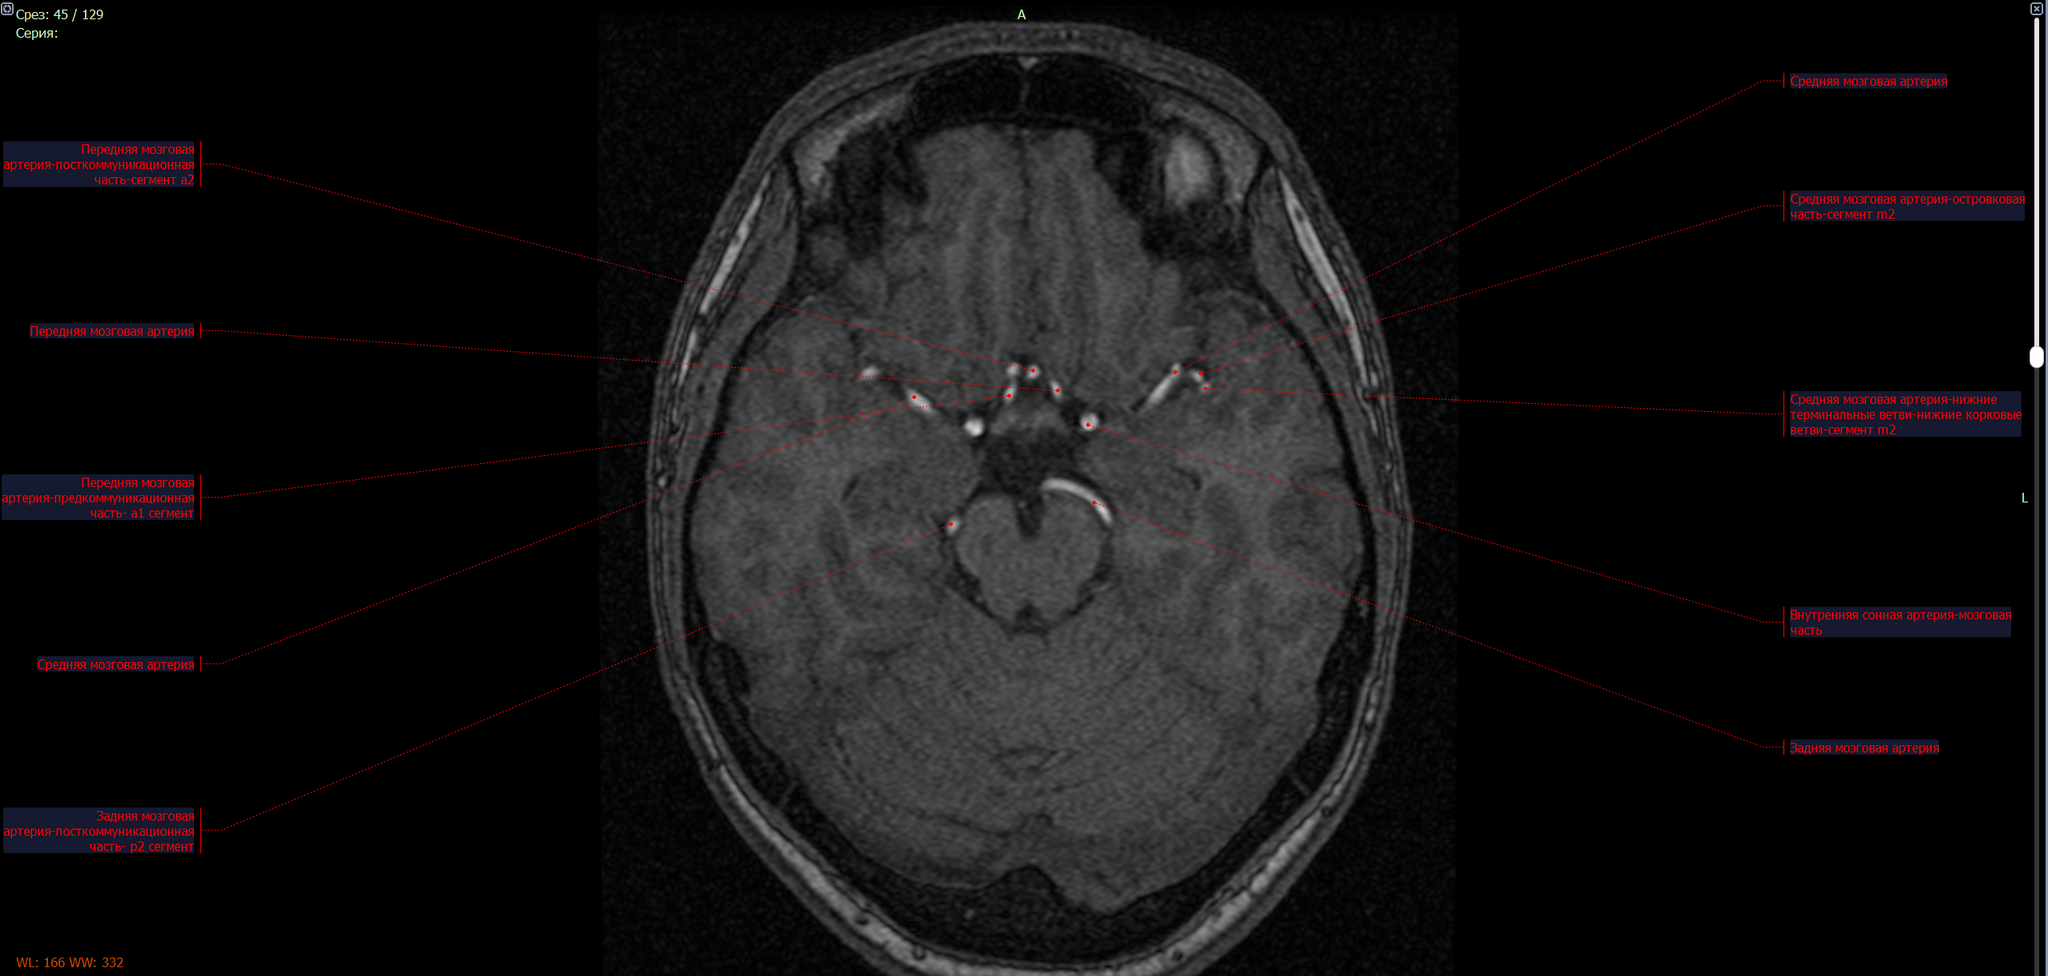

Расположение: Средняя мозговая артерия (a. cerebri media) – одна из основных ветвей внутренней сонной артерии, кровоснабжающая большую часть латеральной поверхности мозга.

МР-картина мешотчатой аневризмы левой средней мозговой артерии на границе М1\М2 сегментов в области бифуркации размерами до 8.4х5.1 мм.